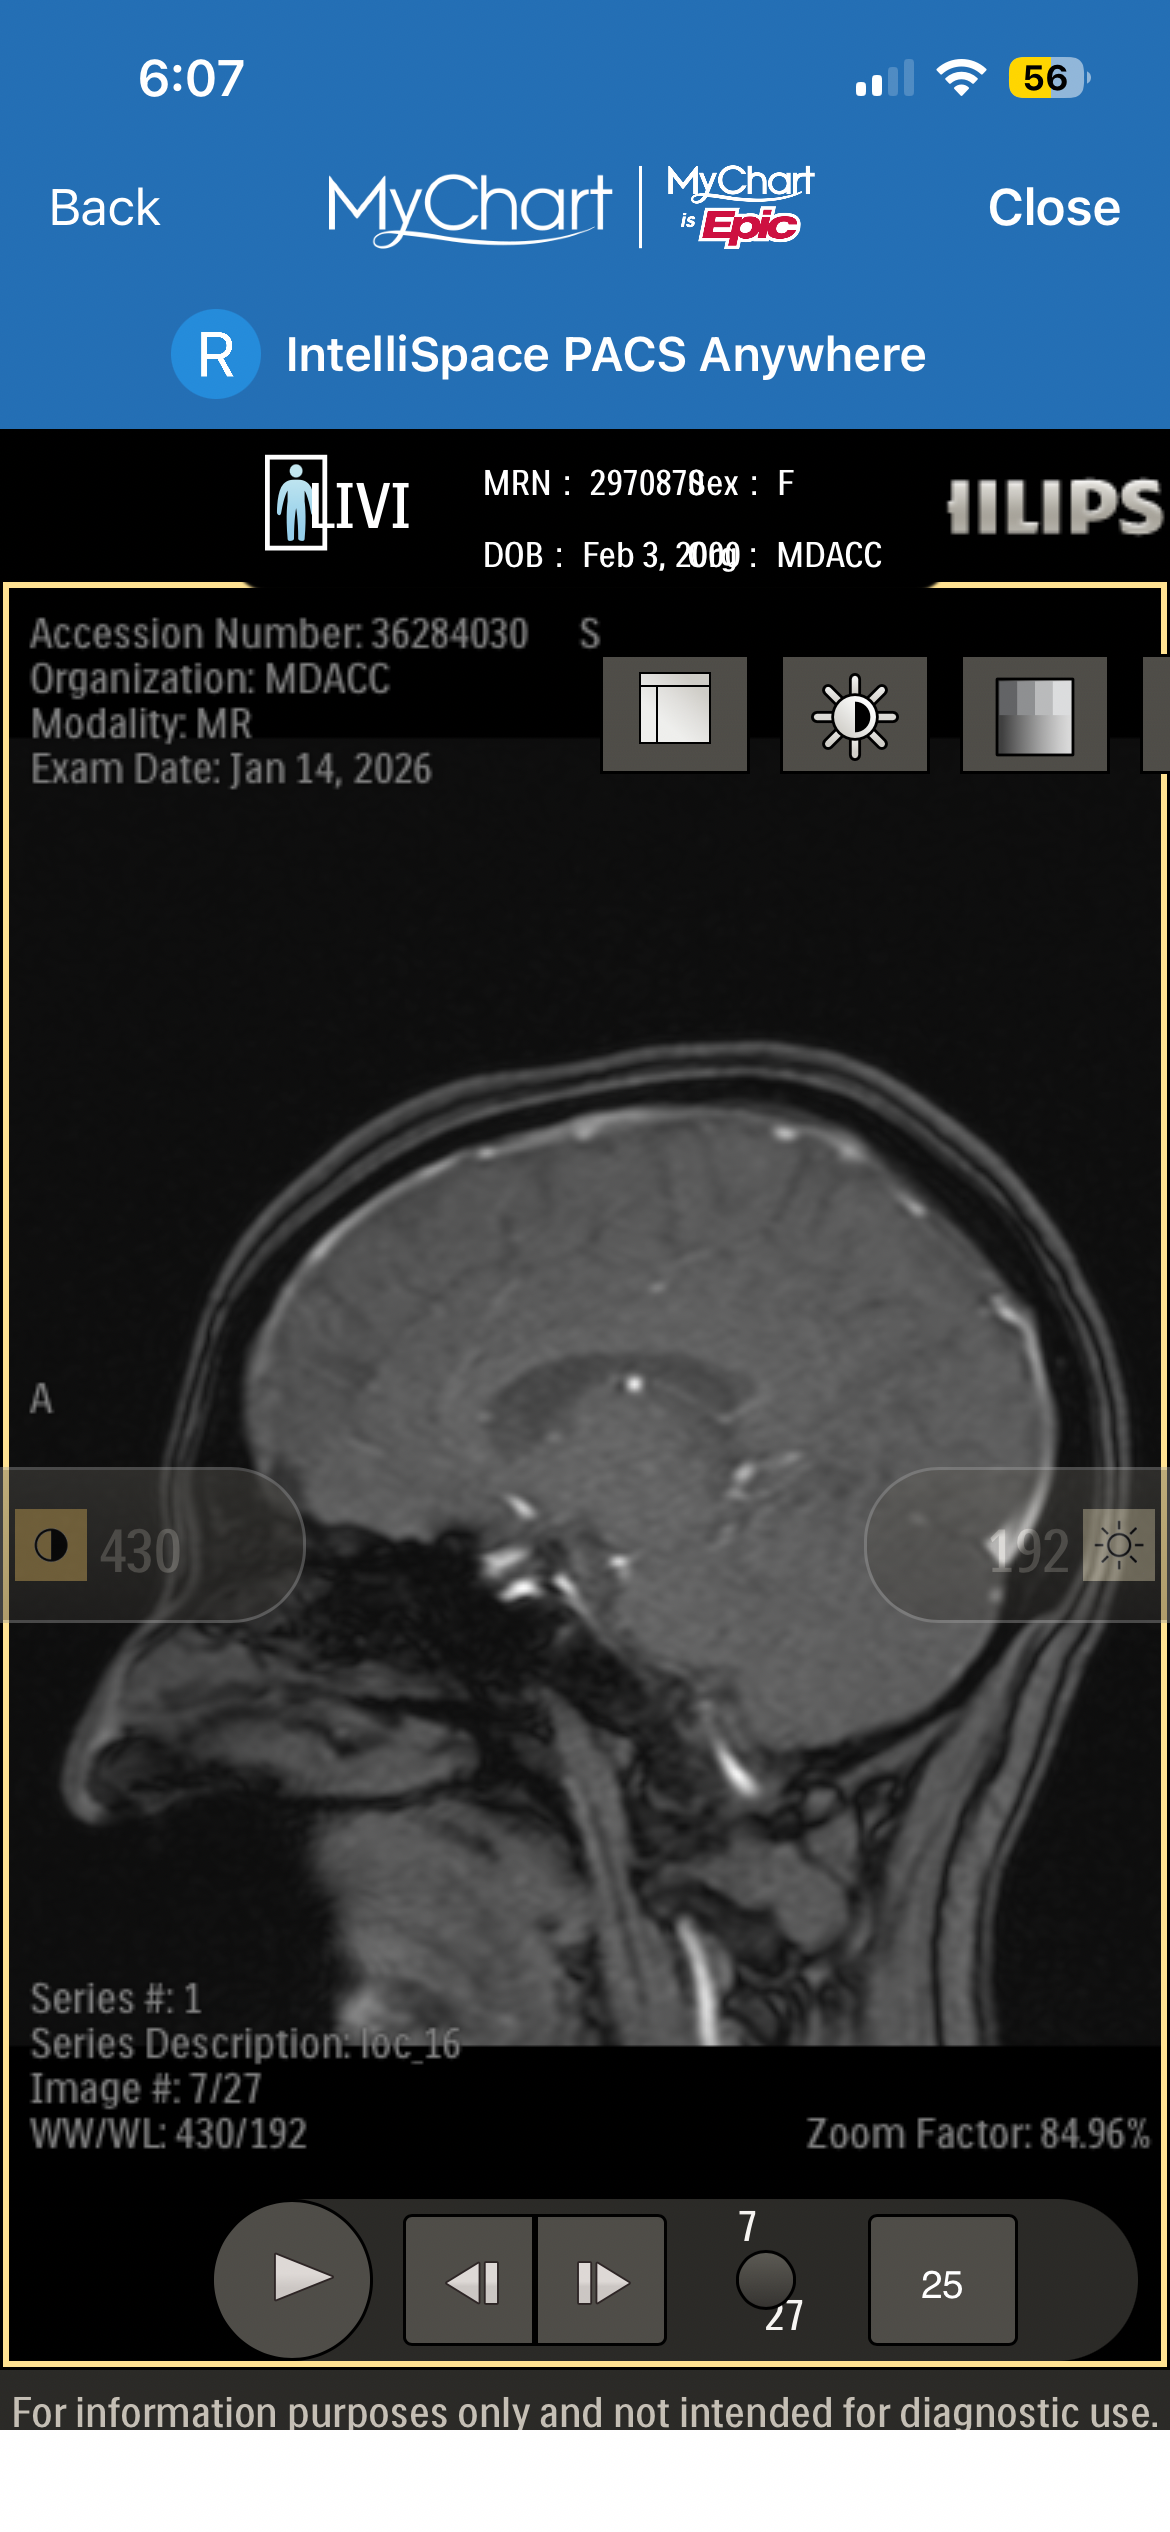

Recently, I was diagnosed with a pituitary brain tumor. Since then, my life—and my family’s—has changed in ways we couldn’t have prepared for. Between medical appointments, testing, treatment planning, and travel for specialized care, the financial and emotional weight has become heavy very quickly.